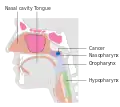

Nasopharyngeal carcinoma (NPC), or nasopharynx cancer, is the most common cancer originating in the nasopharynx, most commonly in the postero-lateral nasopharynx or pharyngeal recess (fossa of Rosenmüller), accounting for 50% of cases. NPC occurs in children and adults. NPC differs significantly from other cancers of the head and neck in its occurrence, causes, clinical behavior, and treatment. It is vastly more common in certain regions of East Asia and Africa than elsewhere, with viral, dietary and genetic factors implicated in its causation.[1] It is most common in males. It is a squamous cell carcinoma of an undifferentiated type. Squamous epithelial cells are a flat type of cell found in the skin and the membranes that line some body cavities. Undifferentiated cells are cells that do not have their mature features or functions.

Nasopharyngeal carcinoma, also known as nasopharyngeal cancer, is classified as a malignant neoplasm, or cancer, arising from the mucosal epithelium of the nasopharynx, most often within the lateral nasopharyngeal recess or fossa of Rosenmüller (a recess behind the entrance of the eustachian tube opening). The World Health Organization classifies nasopharyngeal carcinoma in three types, in order of frequency: Non-keratinizing squamous cell carcinoma; keratinizing squamous cell carcinoma; and basaloid squamous cell carcinoma.[14] The tumor must show evidence of squamous differentiation; with the non-keratinizing type (also known as lymphoepithelioma), the tumor is most strongly associated with Epstein–Barr virus infection of the cancerous cells.[15]

Staging

Staging of nasopharyngeal carcinoma is based on clinical and radiologic examination. Most patients present with Stage III or IV disease.

Stage I is a small tumor confined to nasopharynx.

Stage II is a tumor extending in the local area, or that with any evidence of limited neck (nodal) disease.

Stage III is a large tumor with or without neck disease, or a tumor with bilateral neck disease.

Stage IV is a large tumor involving intracranial or infratemporal regions, an extensive neck disease, and/or any distant metastasis. [16]